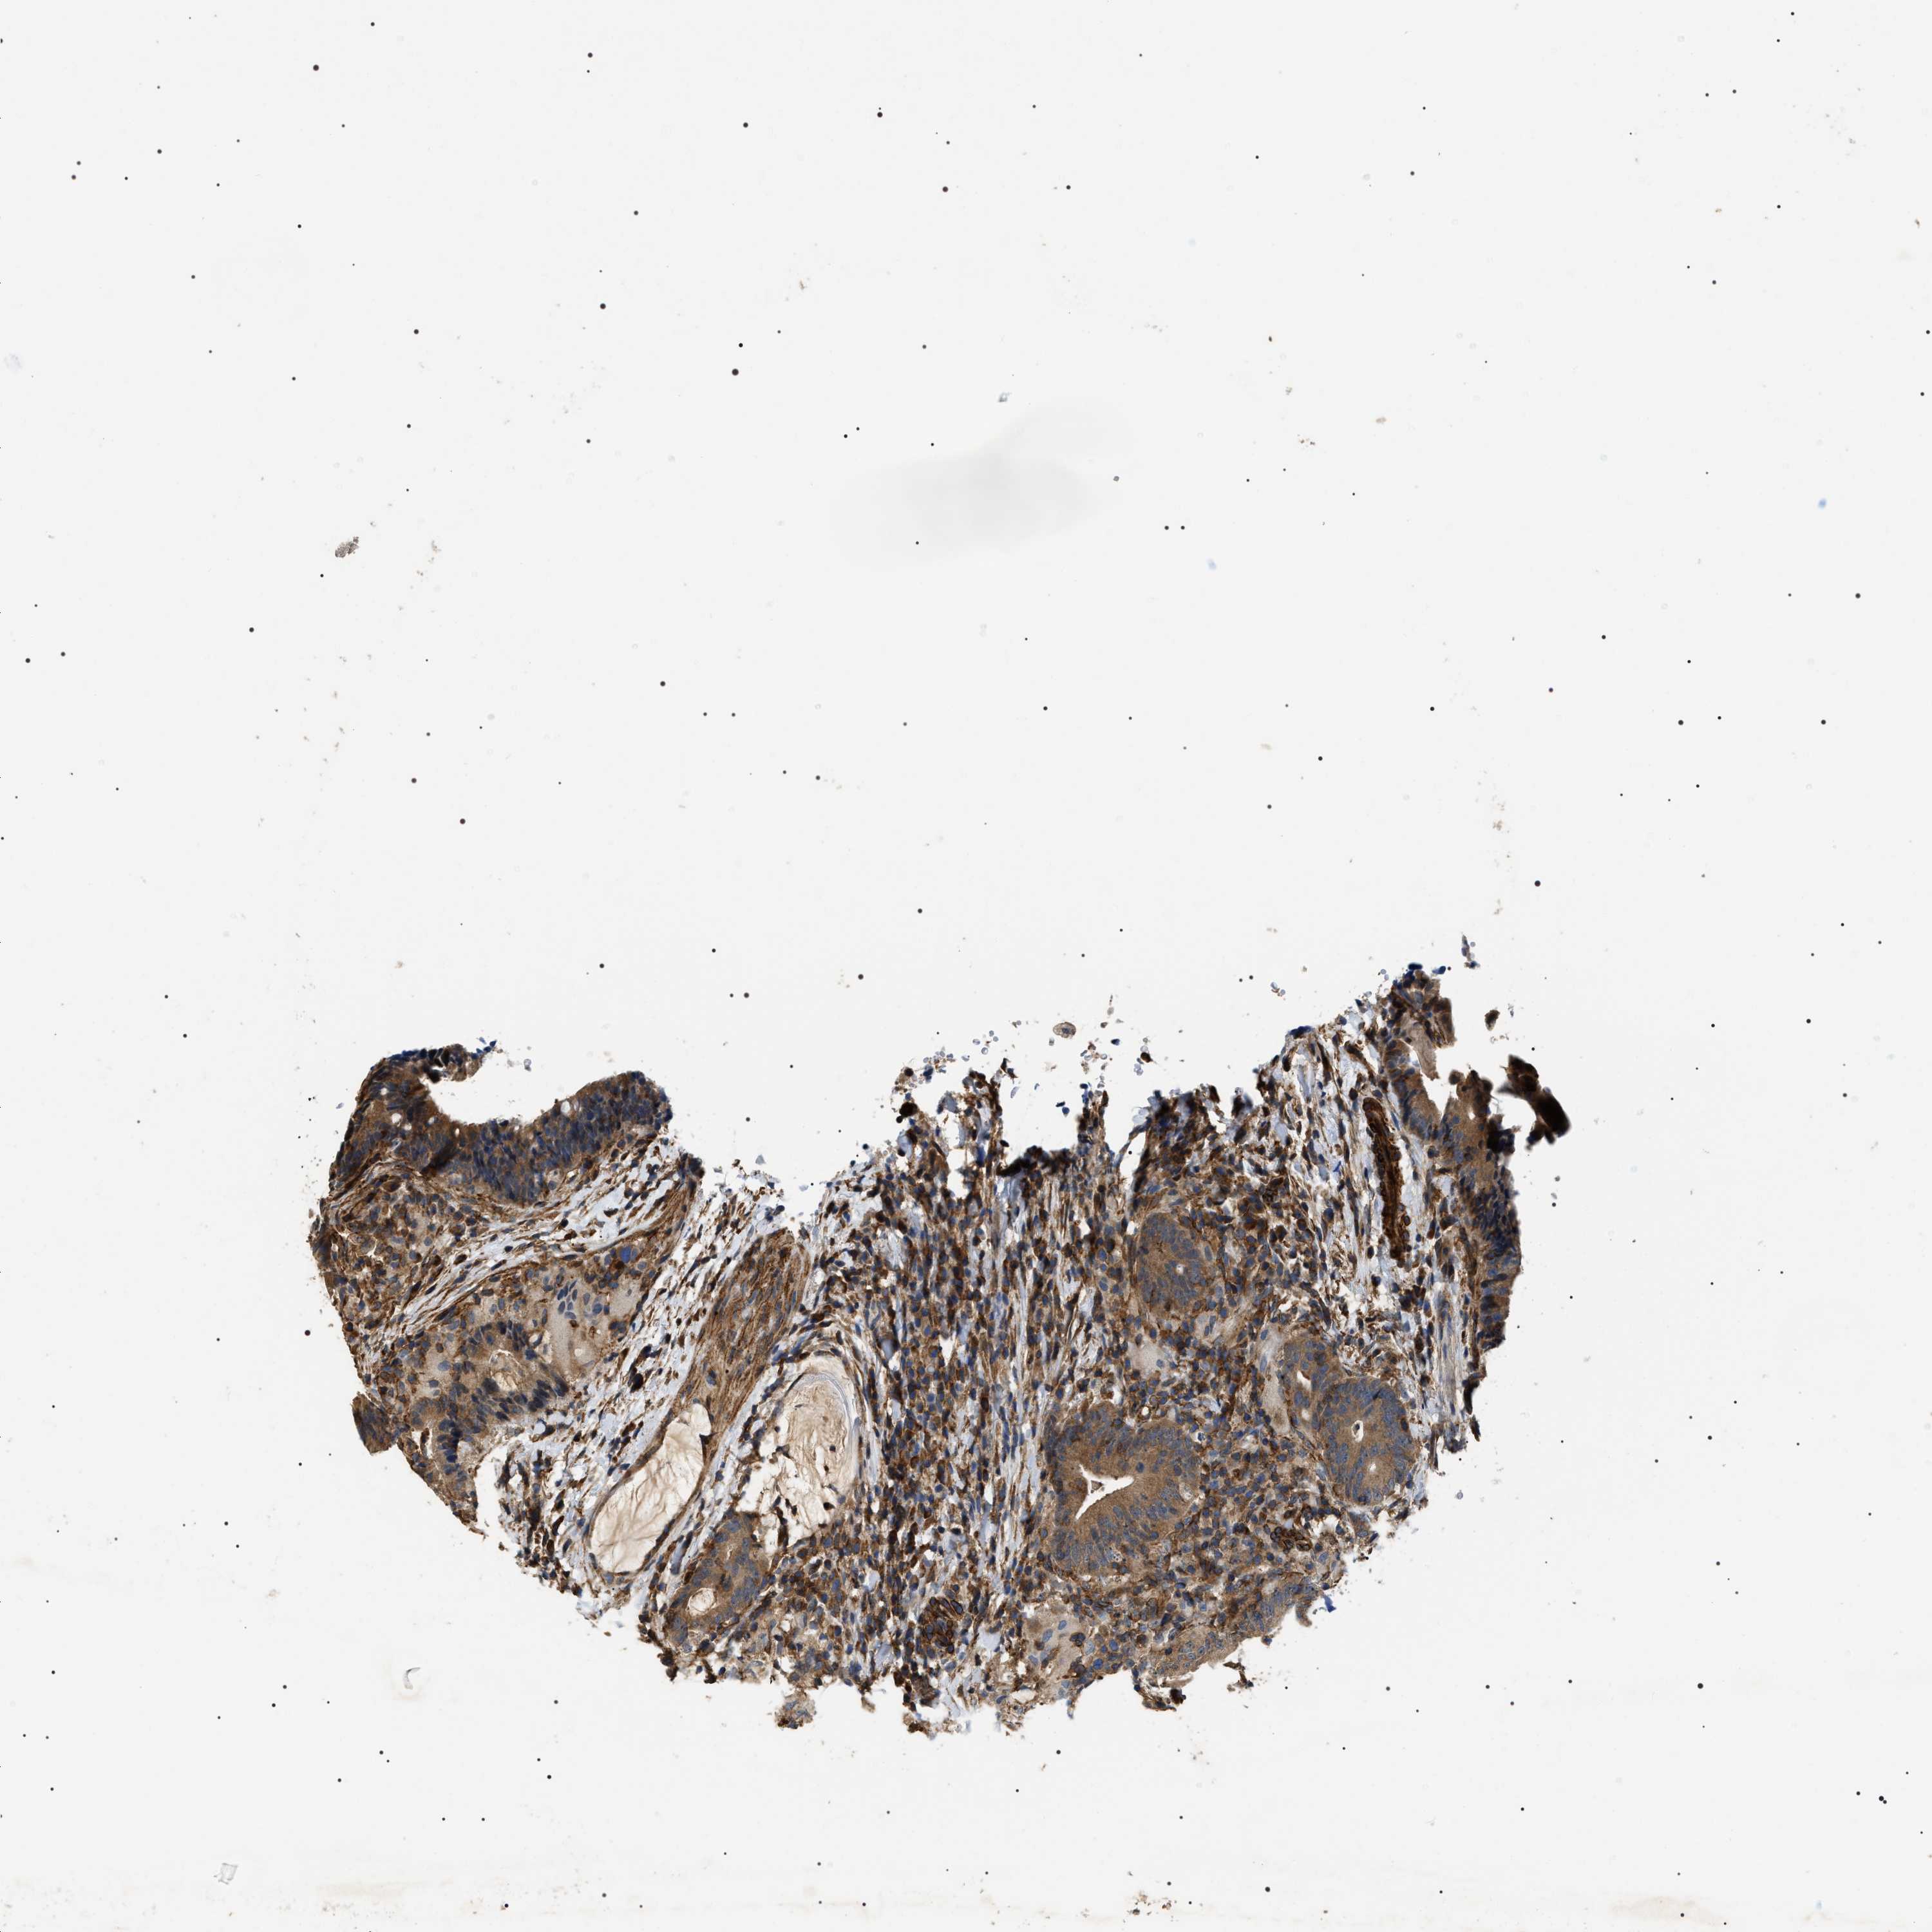

RECTUM ADENOCARCINOMA (TCGA) - Interactive survival scatter ploti

The Survival Scatter plot shows the clinical status (i.e. dead or alive) for all individuals in the patient cohort, based on the same data that underlies the corresponding Kaplan-Meier plots. Patients that are alive at last time for follow-up are shown in blue and patients who have died during the study are shown in red.

The x-axis shows the expression levels (FPKM) of the investigated gene in the tumor tissue at the time of diagnosis. The y-axis shows the follow-up time after diagnosis (years). Both axes are complimented with kernel density curves demonstrating the data density over the axes. The top density plot shows the expression levels (FPKM) distribution among dead (red) and alive patients (blue). The right density plot shows the data density of the survived years of dead patients with high and low expression levels respectively, stratified using the cutoff indicated by the vertical dashed line through the Survival Scatter plot. This cutoff is automatically defined based on the FPKM cutoff that minimizes the p-score. The cutoff can be changed by dragging the vertical line or by entering a cutoff value in the square labeled "Current cut-off".

Under the Survival Scatter plot the p-score landscape (black curve; left axis) is shown together with dead median separation (red curve; right axis). Dead median separation is the difference in median mRNA expression between patients who have died with high and low expression, respectively. It is calculated as follows: median FPKM expression of dead patients with high expression - median FPKM expression of dead patients with low expression. This is intended to aid the user in visually exploring custom cutoffs and the associated p-scores and dead median separation.

Individual patient data is displayed and can be filtered by clicking on one or more of the category buttons on the top of the page. Categories describing expression level and patient information include: high, low, alive, dead, female, male and tumor stages. The scale of the x-axis can be toggled between linear and log-scale by clicking on the "x log" button. Mouse-over function shows TCGA ID, patient information and mRNA expression (FPKM) for each patient.

& Survival analysisi

Kaplan-Meier plots summarize results from analysis of correlation between mRNA expression level and patient survival. Patients were divided based on level of expression into one of the two groups "low" (under cut off) or "high" (over cut off). X-axis shows time for survival (years) and y-axis shows the probability of survival, where 1.0 corresponds to 100 percent.

ZC3HAV1L is not prognostic in Rectum Adenocarcinoma (TCGA)

Best expression cut offi

Based on the FPKM value of each gene, patients were classified into two groups and association between prognosis (survival) and gene expression (FPKM) was examined. The best expression cut-off refers the FPKM value that yields maximal difference with regard to survival between the two groups at the lowest log-rank P-value. Best expression cut-off was selected based on survival analysis .

When clicking on this number, the vertical dashed line indicating cut-off, the interactive survival plot, and the Kaplan-Meier curve will be adjusted to show results based on the best expression cut-off.

: 3.69

Median expressioni

Median expression refers to the median FPKM value calculated based on the gene expression (FPKM) data from all patients in this dataset. When clicking on this number, the vertical dashed line indicating cut-off, the interactive survival plot, and the Kaplan-Meier curve will be adjusted to show results based on the median expression.

: N/A

P scorei

Log-rank P value for Kaplan-Meier plot showing results from analysis of correlation between mRNA expression level and patient survival.

N/A

5-year survival highi

5-year survival for patients with higher expression than the expression cutoff.

For melanoma and glioma, 3-year survival is shown.

5-year survival lowi

5-year survival for patients with lower expression than the expression cutoff.

TCGA RNA samplesi

RNA-seq data is reported as average FPKM (number Fragments Per Kilobase of exon per Million reads), generated by the The Cancer Genome Atlas (TCGA) .

Normal distribution across the dataset is visualized with box plots, shown as median and 25th and 75th percentiles. Points are displayed as outliers if they are above or below 1.5 times the interquartile range. FPKM values of the individual samples are presented next to the box plot.

Average pTPM 4.8

Number of samples 88